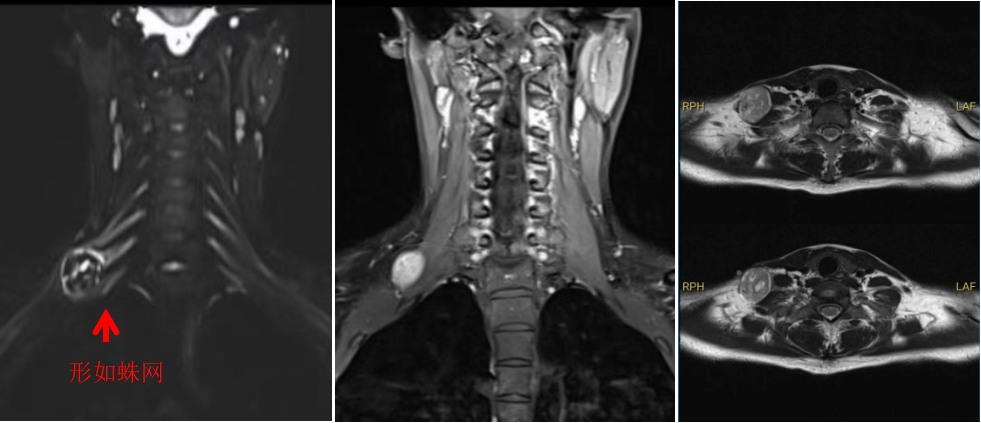

图1

手术由林飞跃医生主刀,团队医生相互配合。由于王女士的肿瘤生长于颈部重要神经丛之中,就宛如盘踞在“蜘蛛网”上(图1),给手术带来了巨大的挑战。医生们如同在一片错综复杂的神经网络中寻找出路,每一步操作都需要格外谨慎,生怕触碰到任何一根关键的神经纤维。林医生一点点地将肿瘤与周围的神经组织分离,经过近两个小时的紧张手术,将肿瘤完整切除。术后,王女士上肢功能恢复完好。